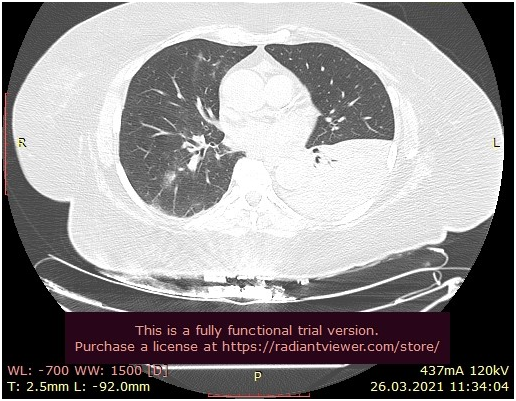

In this study we have 7 COVID positive patients from our hospital in time period from 18 November 2020 to 21 April 2021, four male and three female patients. Six of them had surgery intervention but only one was treated conservatively, because of the diagnosis of acute pancreatitis. Three of the Covid patients were admitted by abdominal surgeon, three of them were admitted by trauma surgeon and one of the patients were admitted by vascular surgeon. Before the surgical intervention we tested the patients and all of them had PCR test positive. When we analyze symptoms three patients were asymptomatic and four of them had COVID 19 related symptoms-dyspnea with low saturation and fever. Four symptomatic patients had COVID 19 pneumonia on RTG and one symptomatic patient had COVID 19 pneumonia on CT lungs. On laboratory analysis four of the patients show lymphocytopenia, low serum iron levels, high level of CRP and D-dimer. Six of the patients who went to surgical intervention, were treated with antibiotics and anticoagulant therapy. Patients who went to abdominal surgery had diagnosis of liver echinococcosis and adhesive ileus, but the third patient was with acute pancreatitis and was treated conservatively. Patients who went to trauma surgery had diagnosis of hip fracture, another patient had hip fracture and pedal skin necrosis and third patient was with radial fracture. Patient admitted on vascular surgery had diagnosis of gangrene caused by diabetic angiopathy. Three patients who were operated by trauma surgeon had successful operation, two of them were released home after few days, and the third female patient who was elderly (80year old) and despite RTG lung with signs of COVID 19 pneumonia, she remained asymptomatic and was transferred to geriatric hospital in stable condition. Patients who were with COVID pneumonia were treated with antibiotics, anticoagulant therapy and three patients who had low saturation were treated with oxygen supply and intravenous corticosteroid therapy. Two patients with COVID 19 pneumonia died from acute respiratory insufficiency and one died from cerebrovascular insult. The patient with acute pancreatitis who was conservatively treated, COVID 19 pneumonia was  diagnose by CT thorax, but the clinical condition worsened and she was transferred to COVID hospital. One of the abdominal patient with diagnose of adhesive ileus  who died from acute respiratory insufficiency had comorbidities DM type 2, St post PCI/Stenting LAD et RCA, St post CVI, and the vascular patient with gangrene and  diabetic angiopathy had comorbidities St post CABG, atherosclerosis generalized and he was the second patient who died from acute respiratory insufficiency, with low O2 saturation 68% and high levels of urea and creatinine in blood, despite being  treated with corticosteroid therapy, oxygen supply, anticoagulant therapy and antibiotics. Female patient with the diagnosis of liver echinococcosis was the third patient who had complication of COVID-19 infection cerebrovascular insult and died from that complication. She had only arterial hypertension as comorbidity (Figures 1 & 2).

Figure 2 CT thorax in 69 old female symptomatic patient with Covid-19 pnemonia.